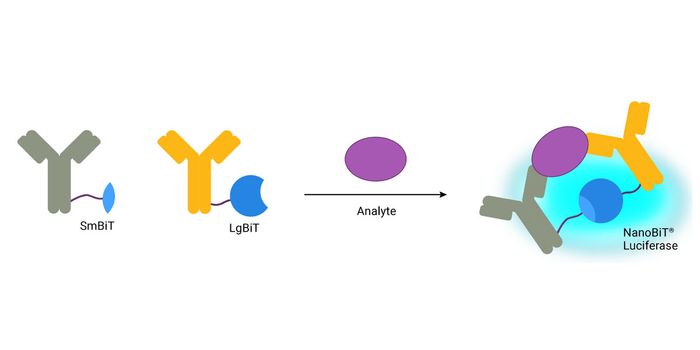

SEP 25, 2023Clinical & Molecular DXImmunoassays are methods for detecting and quantifying analytes within a biological sample based on specific antigen-ant ...